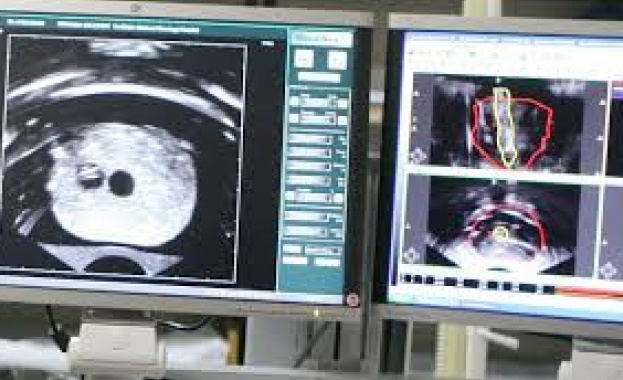

доц. Николов: Ракът е лечимо заболяване

/КРОСС/ Ракът е лечимо заболяване, заяви доц. Манаси Николов, ръководител на направление "Медицинска експертиза" към Националната онкологична болница.

Нашите учени, нашите лекари, които се занимават с лечение на рак, имат много добри постижения. Разликата между преживяемостта в цяла Европа, сравнена с тази в България, е само 10% по-ниска в България, което означава, че ние сме на челно място в световното лечение на рака. Преживяемостта на лекуваните пациенти в нашата болница е с близо 15% по-висока от средната за страната. Ние имаме всички познания, всички методики и умеем да ги прилагаме, обясни доц. Николов в интервю за БНР.

Доц. Николов припомни, че колкото по-рано бъде диагностицирано заболяването, толкова по-добре: Ако ракът бъде открит в първи стадий, начален стадий, преживяемостта е над 90%. Ако бъде открит, когато вече има разсейки в други органи и системи, преживяемостта слиза под 60%.